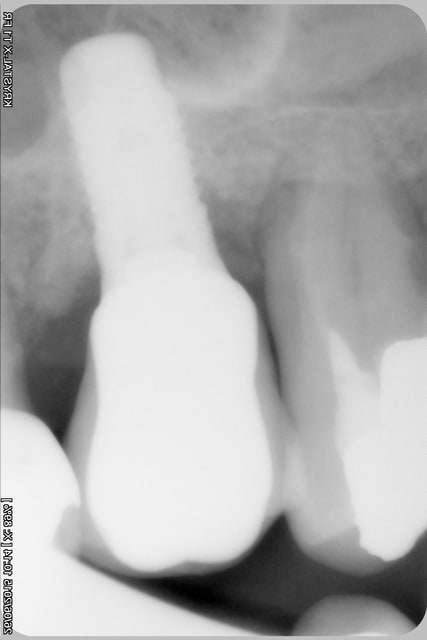

une radio d'implant, pas terrible mais peut être suffisante pour toi Pluton?

> une radio d'implant, pas terrible mais peut être suffisante pour toi Pluton?

pas terrible en effet....

mais bon, il a quand même une bonne tête de SERF EVL N....

heu...les pièces prothétiques c'est chez Global D maintenant...;-)